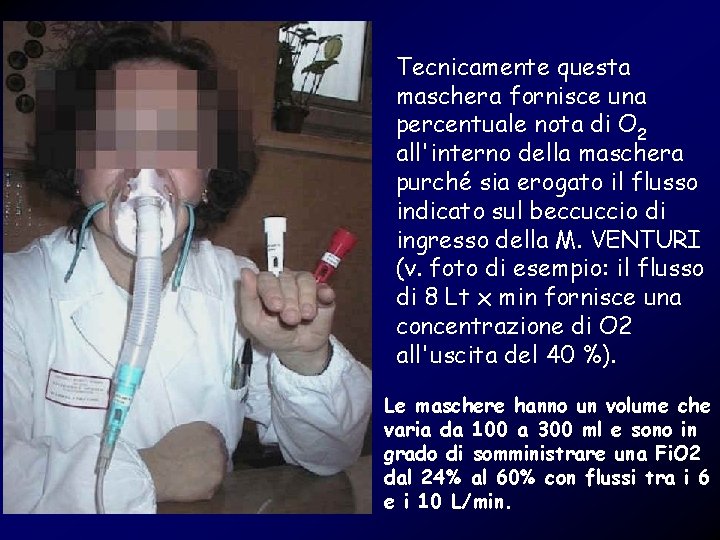

LINEE GUIDA PER IL TRATTAMENTO DELLA TEP • Maschera facciale con sistema Venturi per erogare alte frazioni inspiratorie di ossigeno. • Morfina per alleviare i dolori toracici, la dispnea e la grave apprensione del paziente. Controindicata se la PAS < 100 mm. Hg. • Bicarbonati e. v. nell'acidosi metabolica grave (p. H < 7. 1). • Antibiotici nell'infarto polmonare come profilassi di una possibile infezione della zona necrotica. • Eparina sodica, somministrata precocemente nel sospetto di TEP in attesa della conferma diagnostica per prevenire l' estensione dei trombi e proteggere il paziente dalle recidive di embolia.

Tecnicamente questa maschera fornisce una percentuale nota di O 2 all'interno della maschera purché sia erogato il flusso indicato sul beccuccio di ingresso della M. VENTURI (v. foto di esempio: il flusso di 8 Lt x min fornisce una concentrazione di O 2 all'uscita del 40 %). Le maschere hanno un volume che varia da 100 a 300 ml e sono in grado di somministrare una Fi. O 2 dal 24% al 60% con flussi tra i 6 e i 10 L/min.

LINEE GUIDA PER IL TRATTAMENTO DELLA TEP • Maschera facciale con sistema Venturi per erogare alte frazioni inspiratorie di ossigeno. • Morfina per alleviare i dolori toracici, la dispnea e la grave apprensione del paziente. Controindicata se la PAS < 100 mm. Hg. • Bicarbonati e. v. nell'acidosi metabolica grave (p. H < 7. 1). • Antibiotici nell'infarto polmonare come profilassi di una possibile infezione della zona necrotica. • Eparina sodica, somministrata precocemente nel sospetto di TEP in attesa della conferma diagnostica per prevenire l' estensione dei trombi e proteggere il paziente dalle recidive di embolia.